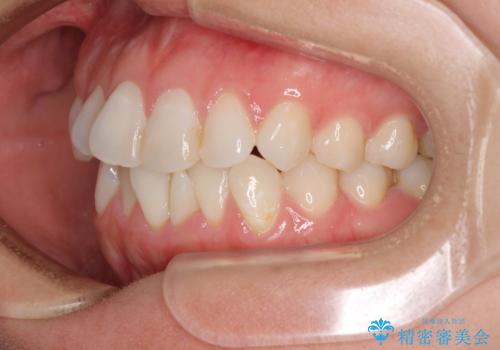

長年気にしていた前歯 インビザラインで目立たず改善

- ワイヤーではない矯正治療があると聞いたとのことで来院された患者様です。

長年前歯のデコボコを気にしていたもののワイヤー矯正に抵抗があり躊躇していたそうですが、インビザラインなら治療してみたいとのことで相談にいらっしゃいました。

インビザライン適用の歯列であったため、歯と歯の間を削るIPRを用いて改善することとしました。

下顎前歯の叢生が顕著な場合、歯列改善後に歯と歯と歯肉の間にブラックトライアングルという隙間ができてしまいます。

軽減することはできますが、完全に解決することは矯正治療のみでは不可能なため、リスクとして事前に周知しておく必要があります。